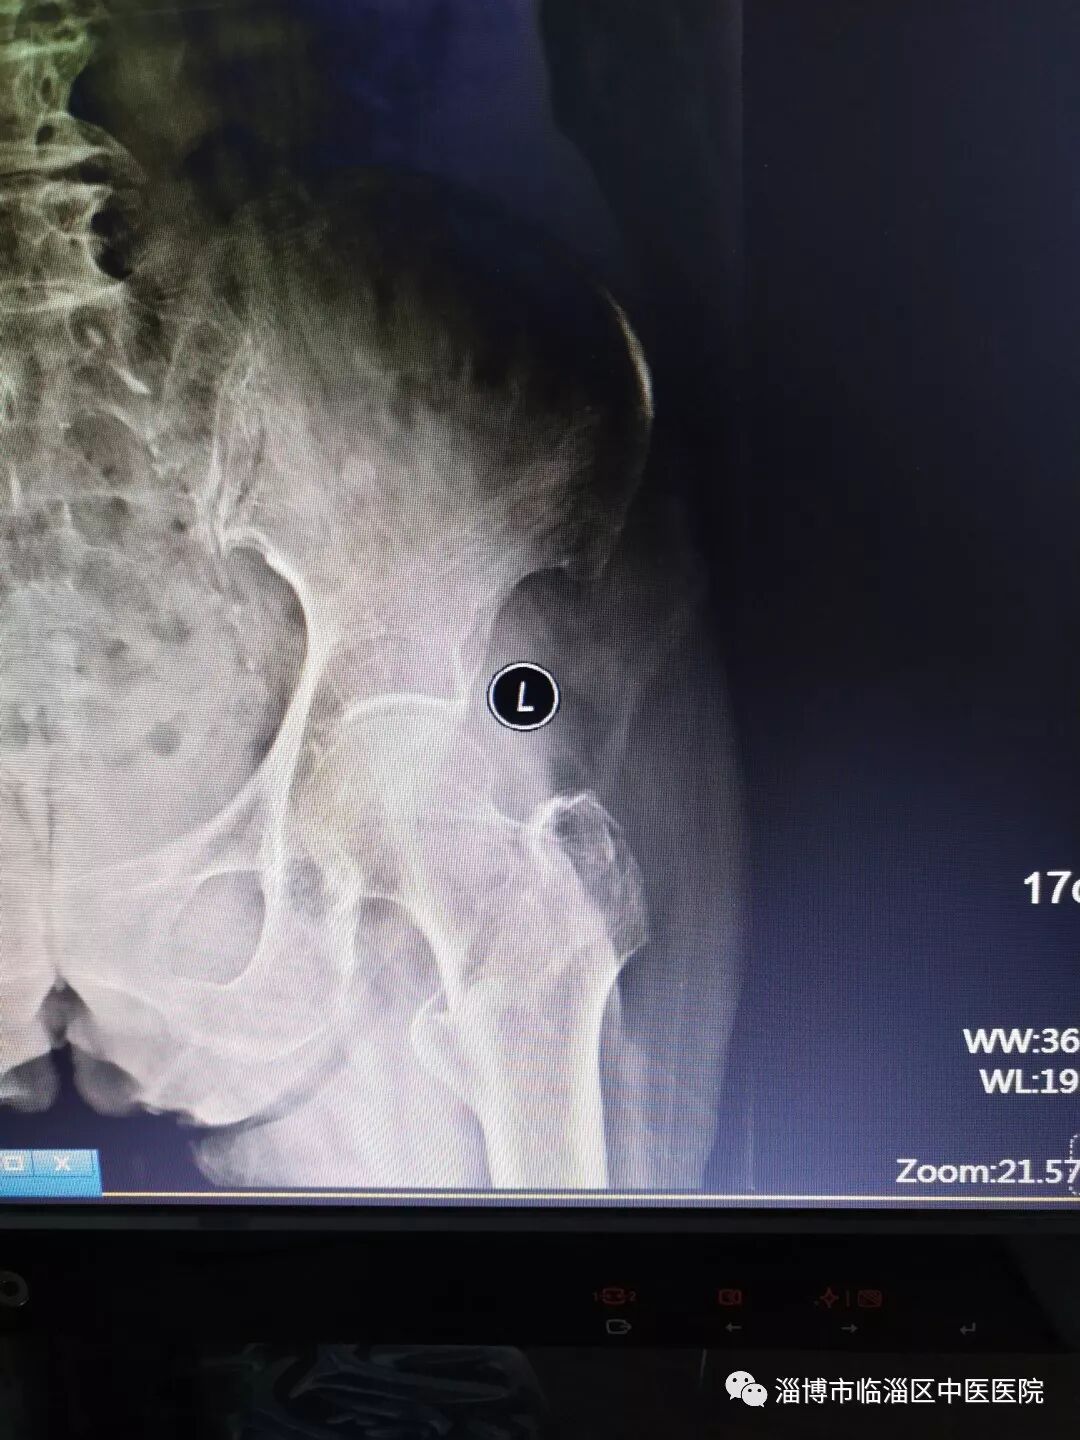

此次收治的患者,张某,91岁,因外伤致左侧股骨颈骨折,合并有高血压病史,肺气肿病史。伤后患者疼痛难忍,为帮助患者解除病痛,改善生活质量,骨科迅速组成了专门的诊疗小组,耐心向家属说明患者病情发展过程,同时依据多年的临床经验及手术病例,从手术前心肺腹检查及实验室检查,到科室会诊协助调理血压及心肺功能,再到术后准备预防并发症的发生,制定了周密科学的医疗计划。

手术前